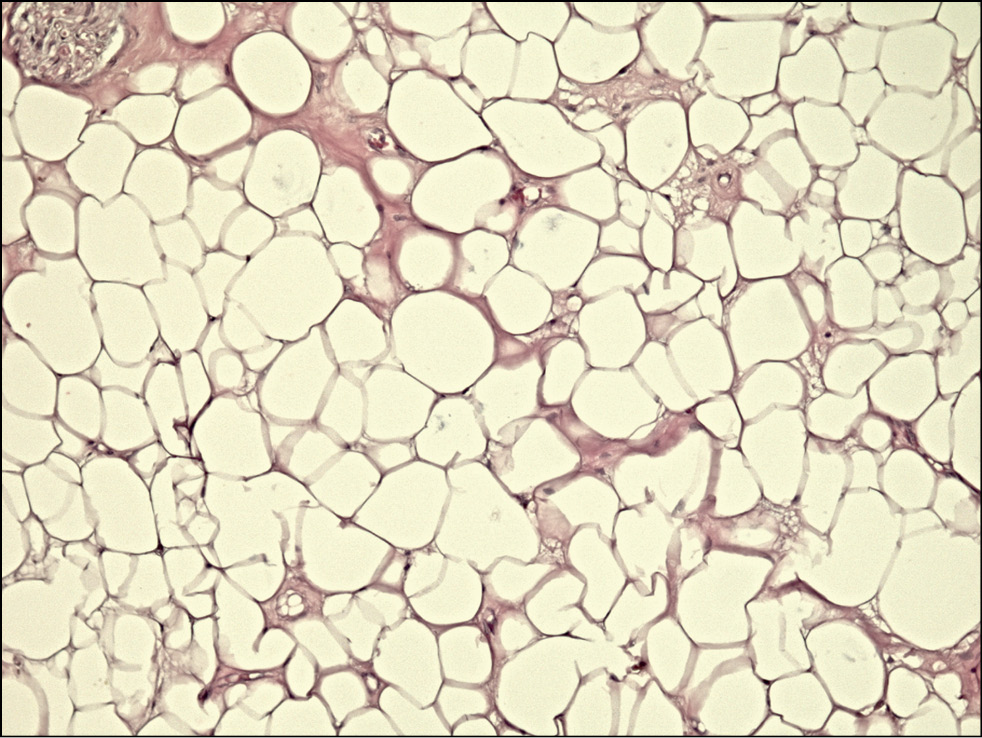

Ещё 4 биоптата характеризовались фрагментами жировой ткани, имелись признаки отёка и гиперплазии (рис. 7).

Рис. 7. Гистологический препарат леватора с разрастанием жировой ткани при приобретённом птозе верхнего века. Окраска — гематоксилин/эозин, увеличение 100х.